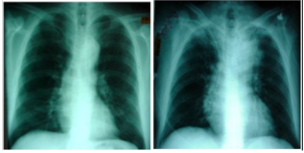

What are the two methods to study the mediastinum?

What are some common examples for widening of the mediastinum?